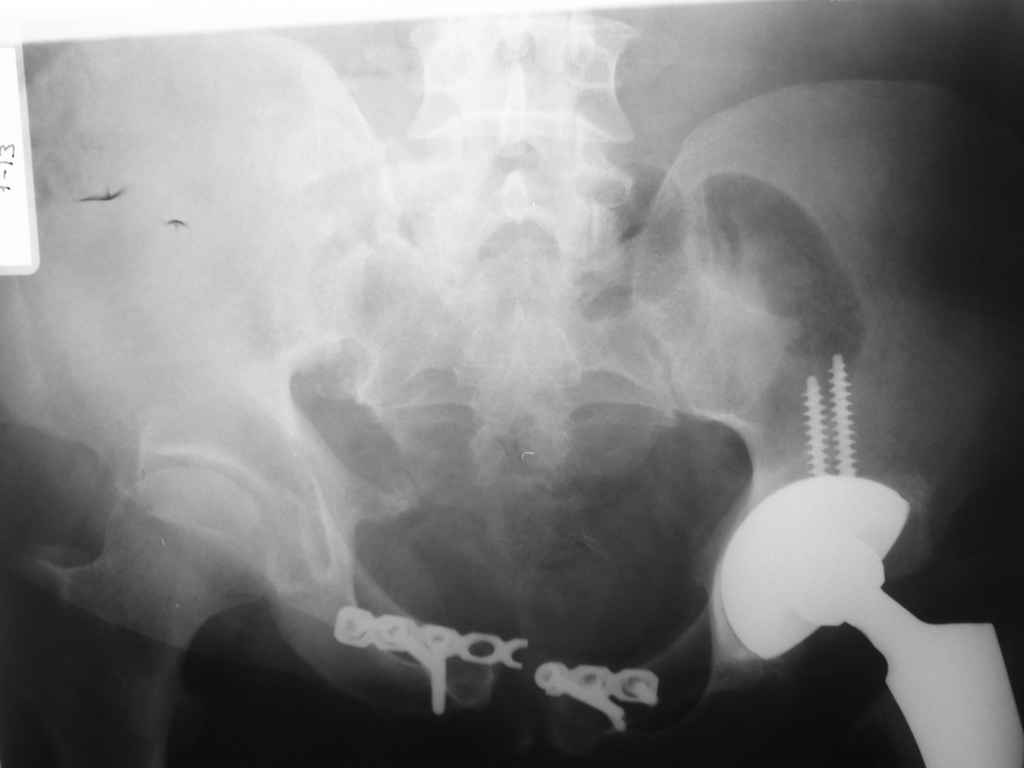

прилагаю пример с такой же давностью травмы, репонировали аппаратом

> в аппарате или одномоментно открыто. Лично я склоняюсь к аппаратному лечению на первом этапе.

задача непростая, если мало опыта в этом деле, подумайте еще раз